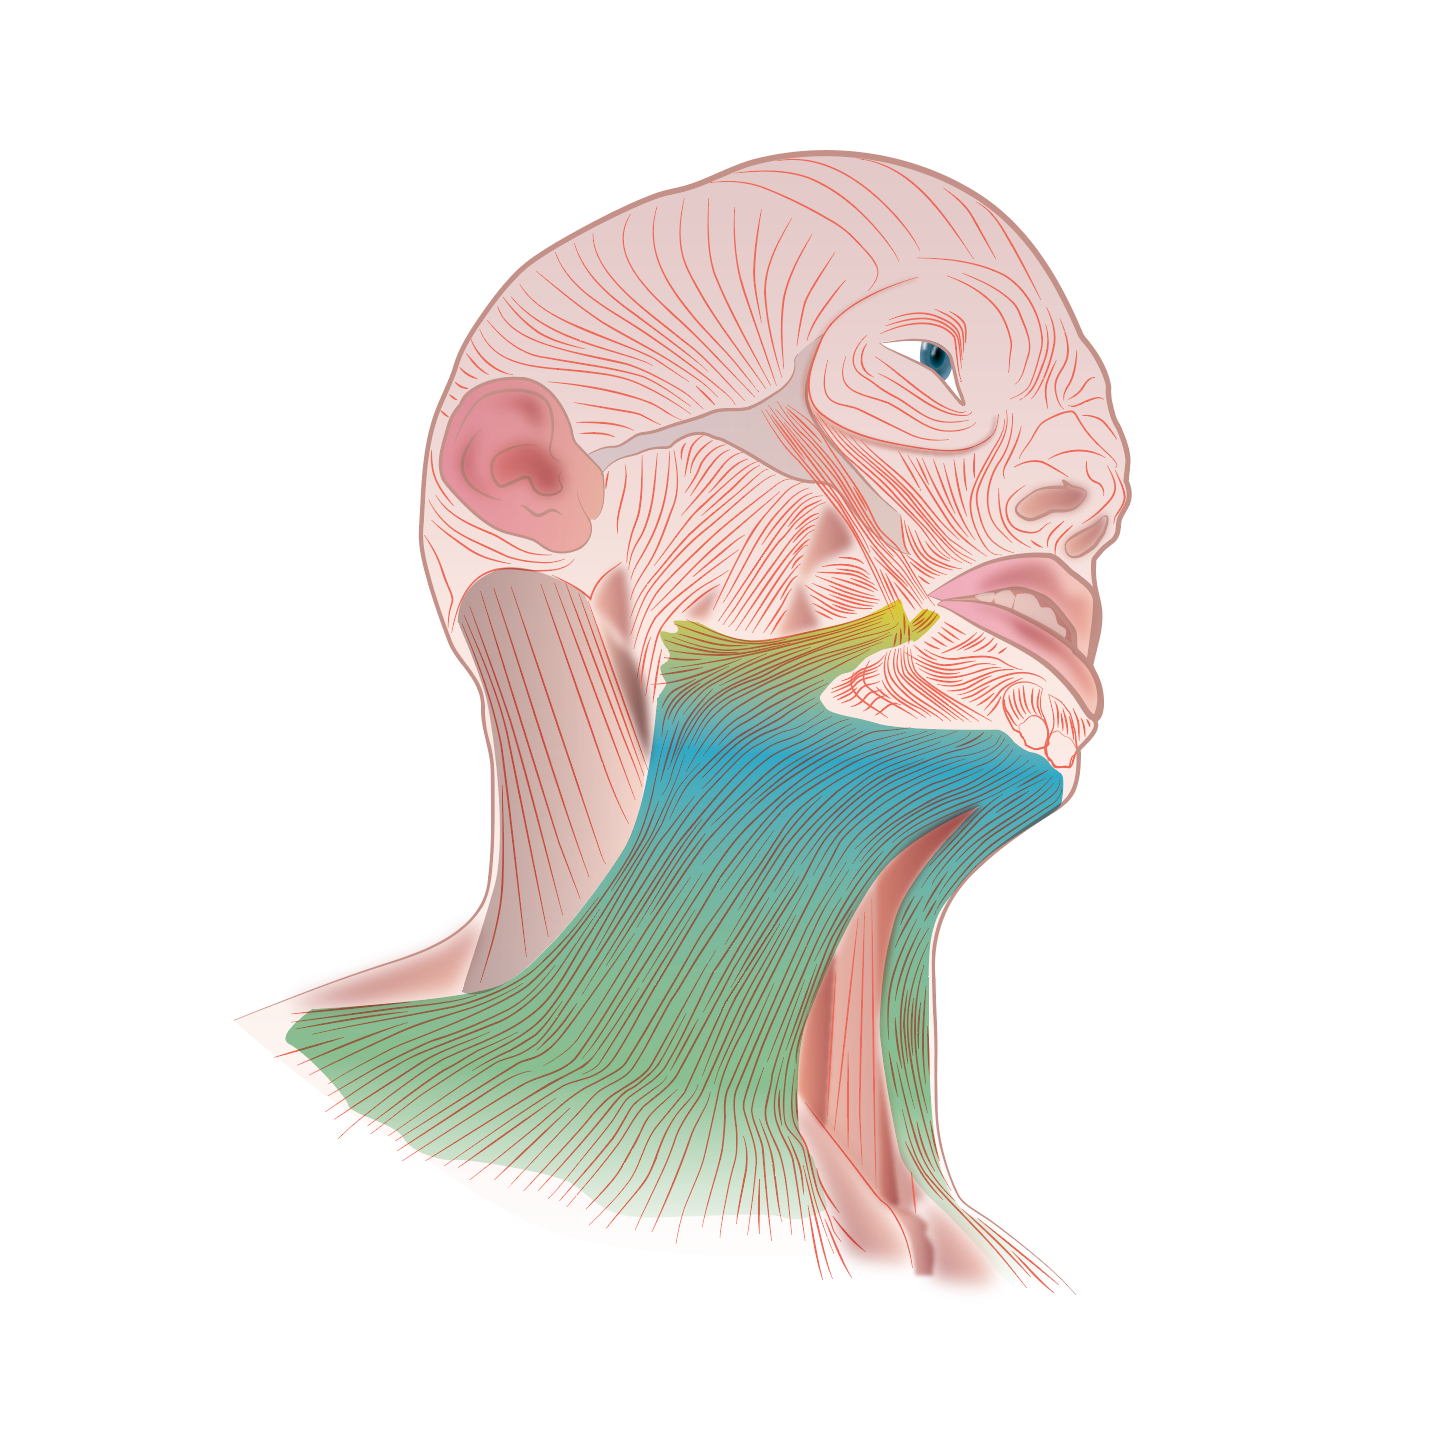

Músculos de la cara